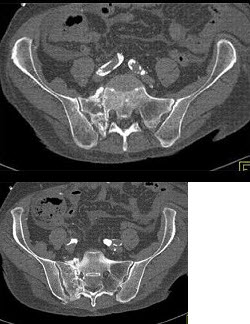

5、单项选择题

根据所提供的图像,最可能的诊断是()

A.肠系膜囊肿

B.脂肪瘤

C.淋巴瘤

D.陈旧性血肿

E.以上都不是

点击查看答案